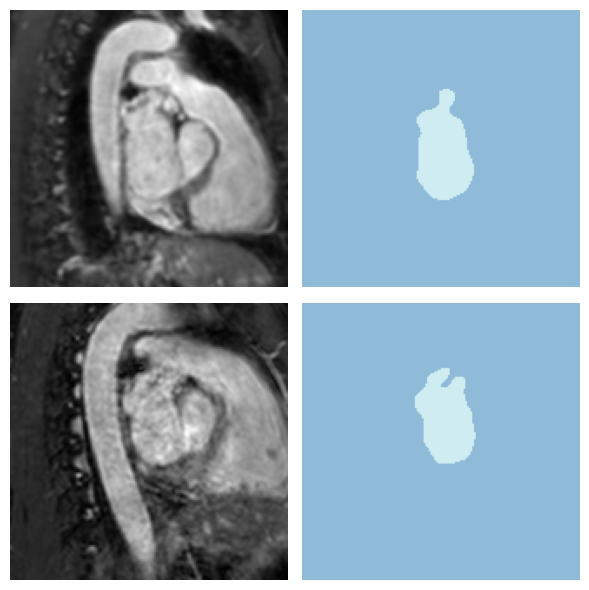

# Visualize a batch of patches

batch = next(iter(dls.train))

x, y = batch

print(f"Batch shape - Image: {x.shape}, Mask: {y.shape}")Batch shape - Image: torch.Size([4, 1, 160, 160, 80]), Mask: torch.Size([4, 1, 160, 160, 80])

dls.show_batch(anatomical_plane=2, max_n=2, overlay=False)